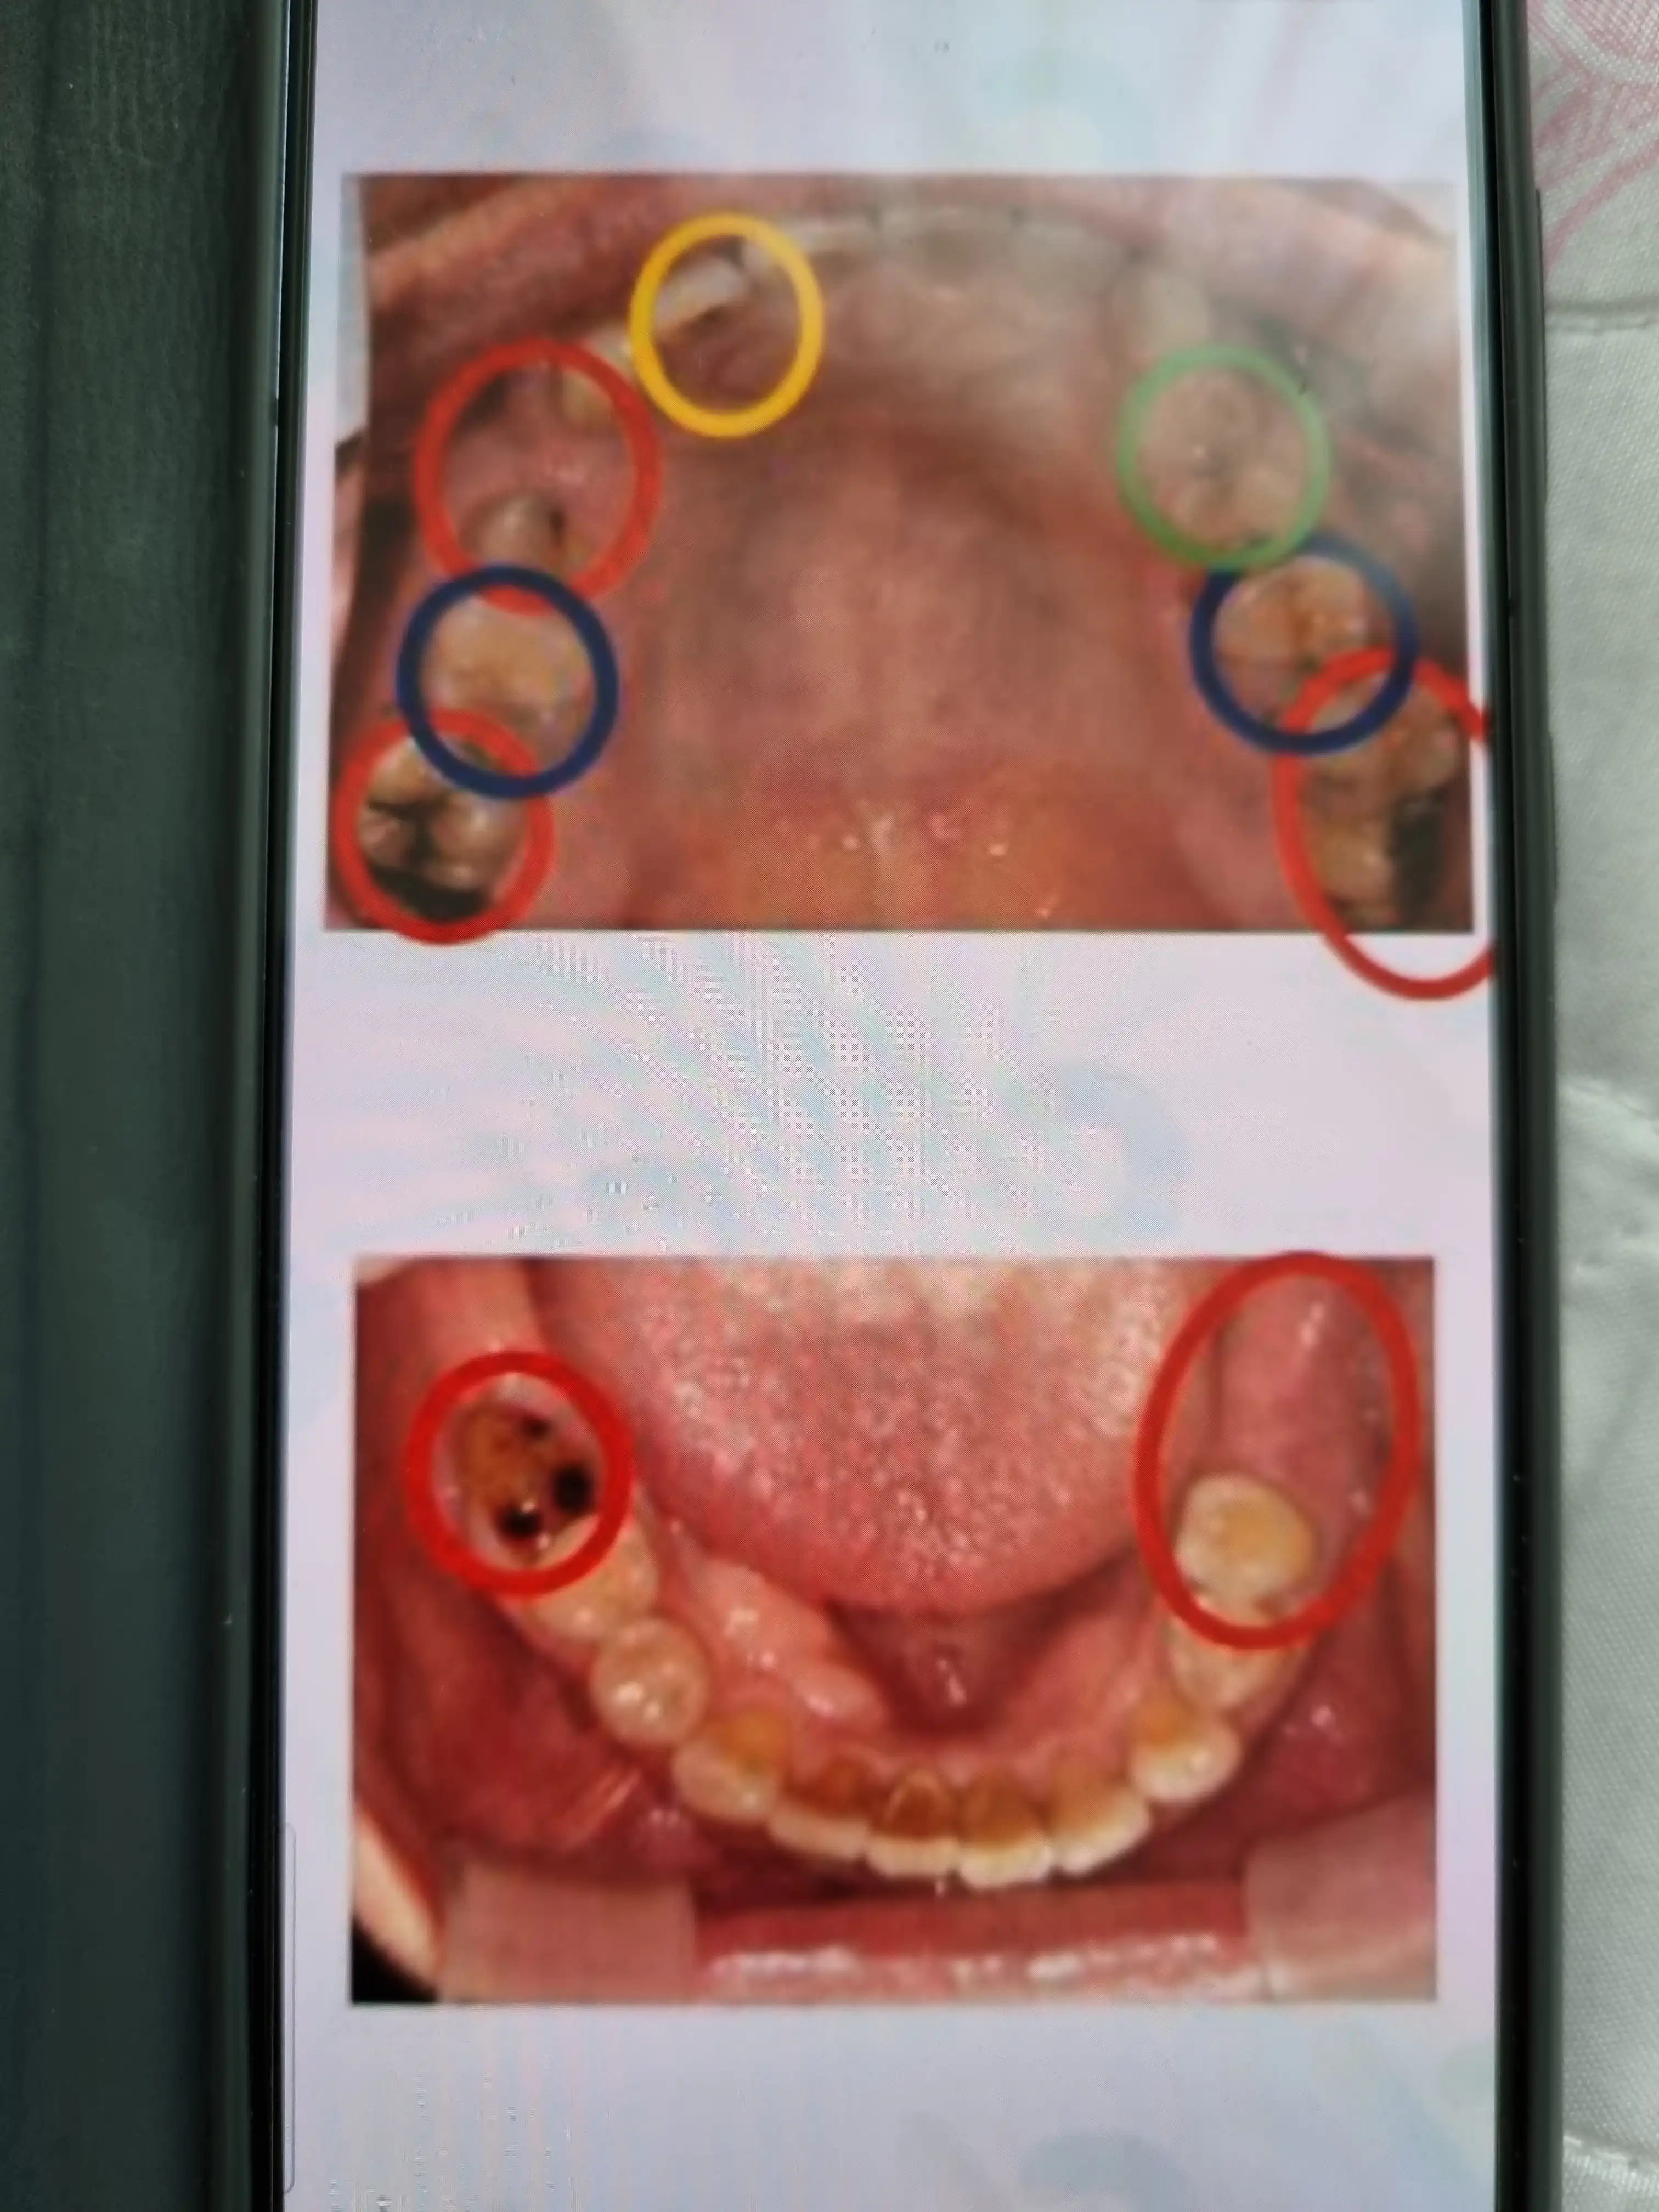

방문 인증 완료 #★무삭제 라미네이트 38.5만원

전

후 시술친절하고세밀하게 잘해주셔서감사합니다 다른곳에서도 많이홍보하고싶위서홍보중 너무잘해주십니다